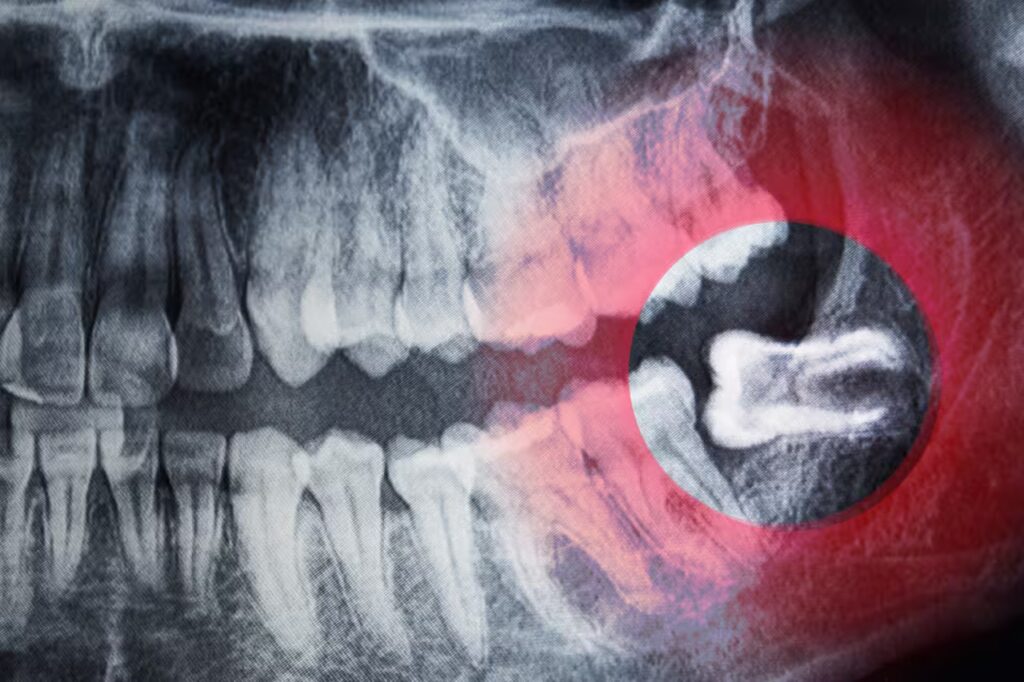

- Consultation and X-ray: Your dentist will begin by assessing your wisdom teeth with an X-ray to determine their position and whether they need to be removed.